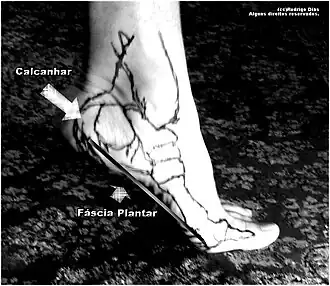

| Demonstração da fáscia plantar. Local onde ocorre a Fasceíte plantar. | |

Fibromatose da fáscia plantar, fasciíte plantar ou fascite plantar (também conhecida como síndrome do Esporão do Calcâneo) é um distúrbio doloroso comum que afeta o calcanhar e a planta do pé. Trata-se de uma desordem no local de inserção dos ligamentos no osso e se caracteriza pela cicatrização, inflamação ou destruição estrutural da fáscia plantar do pé. É frequentemente causada pela lesão por esforço repetitivo da fáscia plantar, que se intensifica com exercício físico, peso ou idade. Embora originalmente a fascite plantar tenha sido pensada como um processo inflamatório, estudos recentes têm demonstrado alterações estruturais mais condizentes com processos degenerativos. Como resultado das novas observações, parte da comunidade acadêmica tem defendido a mudança do nome desta condição para "fasciose plantar".[1]

A causa da fascite plantar é pouco compreendida e acredita-se que provavelmente haja a participação de vários fatores.[15] A fáscia plantar é uma faixa fibrosa espessa de tecido conjuntivo que se origina da tuberosidade do osso calcâneo. A partir daí, a fáscia se estende ao longo da sola do pé, antes de se inserir na base dos dedos do pé, e sustenta a arcada plantar.[9][11][14]